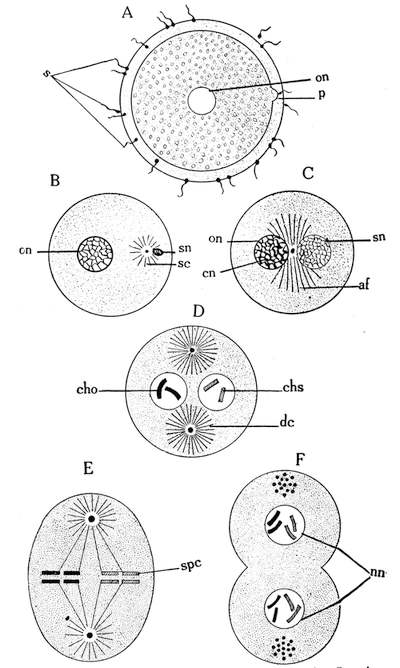

The ovum or even the zygote (i. e., the impregnated ovum) is a single-celled organism and resembles the animals of the first or lowest type in the animal kingdom. The protozoa are nothing else than single-celled animals. Some of them have even a lower structure than the common cell. The Monera, e. g., has neither nucleus nor membrane. The manifestations of life are recognizable only by the possession of the faculties of the assimilation of food and of propagation by segmentation and division.

Like the protozoon, the ovum, immediately after its impregnation, begins to undergo a certain division, by a series of successive segmentations, into 2, then 4, 8, 16, 32, 64, etc., cells. By continuous cell segmentations a great mass, the morula or mulberry, is produced. The structure of the morula corresponds with that of the coelenterata, or the animals of the second type. To this type belong the animals with gemmiparous reproduction, or multiplication by means of buds. The divided animals remain together and form colonies, as e. g. in sponges or corals.

The next event in the formation of the embryo is the blastula. The solid spherical mass of cells becomes hollow like a rubber ball. In the subsequent stage the blastula becomes flat at one pole. By degrees a depression is formed at this point, which becomes deeper step by step, until the inner layer reaches the outer layer, representing half a sphere of two layers, like a collapsed rubber ball. In the farther growth the edges approach the middle line till they finally meet and fuse together. The oval body, called the gastrula, thus consists of two layers, the primitive germinal membranes, the ectoderm and entoderm. The gastrula resembles in its structure that of the worms, or the third type of the animal kingdom.

By certain foldings of the ento- and ectoderm transformations arise, and new organs develop. Two folds of the entoderm19 grow higher, approach each other and finally meet. In this way the embryo consists of four germinal membranes. A certain folding of the ectoderm marks the position of the future backbone in the primitive stripe. A longitudinal furrow marks the origin of the nerve-tube. The different membranes have thus formed several tubes, the chorda dorsalis, the definitive intestinal canal and the abdominal cavity or coelom. The structure of the embryo resembles now more or less that of the animals of the fourth type or the echinodermata.

The membranes which include the intestinal canal soon overgrow on both sides the nerve-tube and the chorda and are then differentiated partly into the bones of the skeleton and partly into the muscles. In the meantime, the vascular spaces develop. At one point of the vascular tube a rhythmical pulsation is observed, representing the primitive heart, similar to that of the mollusca.

A certain fold, the head-fold, arises at the front end of the embryo by the bending of the spinal column. Beneath the head-fold arise five processes or gills, as in fishes, which later on are transformed into the face of the fetus. Four other processes are budded off from the trunk and subsequently become the extremities. A furrow at the ventral side of the embryo shows the origin of later trachea and lungs. On both sides of the head-fold can be seen two pits for the eyes. At this point, the embryo is in the same stage of development as many arthropoda.

The skeleton begins now to ossify. The heart tube begins to bend and takes the form of an “S.” In this way the tube is turned into an auricle and ventricle as in the amphibia. The ventricle is then divided by a partition as in the reptiles. One part of the nerve-tube is differentiated into three cerebral vesicles, as in birds.

Thus the embryo resembles in its structure at different stages the structure of the different types of the animals of the animal kingdom. The different formations do not follow the chronological order as described, but, as a rule, they take place synchronously. At the end of the fourth month the fetus is about sixteen centimeters or six inches long and has reached its definite human shape.